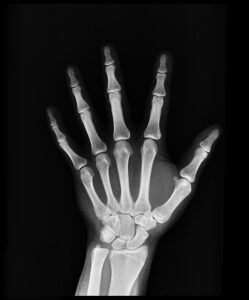

زندگی استئوپنی و پوکی استخوان: چگونه از شکستگیهای استخوانی جلوگیری کنیم؟ پیام جوان: استئوپنی به کاهش تراکم استخوان اشاره دارد که هنوز به اندازهای نیست که به پوکی استخوان تبدیل شود. Read More 2025-01-31

زندگی بررسی روشهایی برای کمک به افزایش تراکم استخوانها پیام جوان: کاهش تراکم استخوانها به این معنی است که فرد در معرض خطر پوکی استخوان به عنوان یک بیماری Read More 2024-04-10

راه های تشخیص ابتلا به پوکی استخوان در بدن پیام جوان: پوکی استخوان یک بیماری نامرئی محسوب میشود؛ چراکه تا زمانی که یک استخوان نشکند، علامتی از خود بروز Read More 2022-12-21